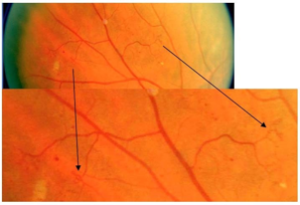

视网膜内微血管异常(IRMA)

视网膜内微血管异常(IRMA)是扭曲扩展的视网膜内血管片段。

视网膜上的点状微血管瘤和视网膜表面清晰可见的新生血管都不属于视网膜内微血管异常。

▲ 视网膜内微血管异常(A)

▲ 视网膜内微血管异常(B)